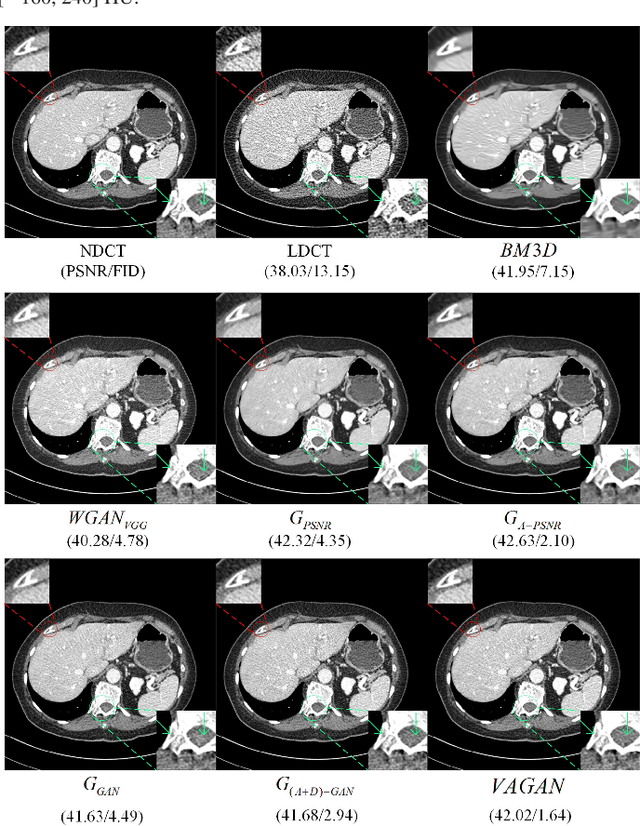

Abstract:Noise and artifacts are intrinsic to low dose CT (LDCT) data acquisition, and will significantly affect the imaging performance. Perfect noise removal and image restoration is intractable in the context of LDCT due to the statistical and technical uncertainties. In this paper, we apply the generative adversarial network (GAN) framework with a visual attention mechanism to deal with this problem in a data-driven/machine learning fashion. Our main idea is to inject visual attention knowledge into the learning process of GAN to provide a powerful prior of the noise distribution. By doing this, both the generator and discriminator networks are empowered with visual attention information so they will not only pay special attention to noisy regions and surrounding structures but also explicitly assess the local consistency of the recovered regions. Our experiments qualitatively and quantitatively demonstrate the effectiveness of the proposed method with clinic CT images.